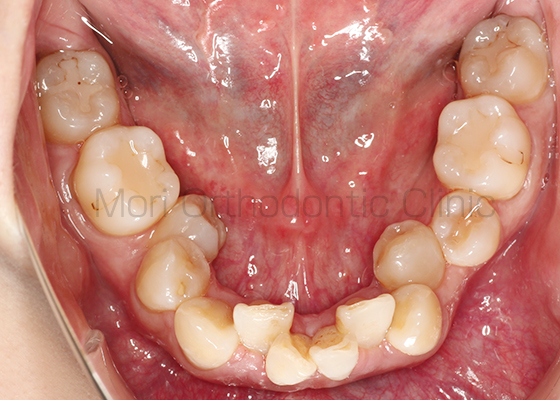

術前